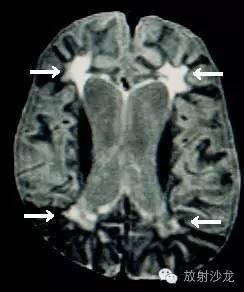

A and B, ADEM. Axial FLAIR spin-echo MR scan shows multifocal subcortical hyperintense foci with confluent white matter disease in basal ganglia. C and D, MS. Axial FLAIR spin-echo MR scans show high signal foci similar to ADEM. MS lesions were more likely enhancing, ovoid, periventricular and perpendicular to the long axis of the ventricles than ADEM lesions.

(A) MRI brain (T2 weighted) in MS showing well demarcated lesions in the region of the periventricular white matter.

(B) MRI brain (T2 weighted) in ADEM showing a large mass-like lesion in the white matter.

(C) MRI brain in ADEM showing multiple large lesions with poorly defined margins and relative periventricular sparing.